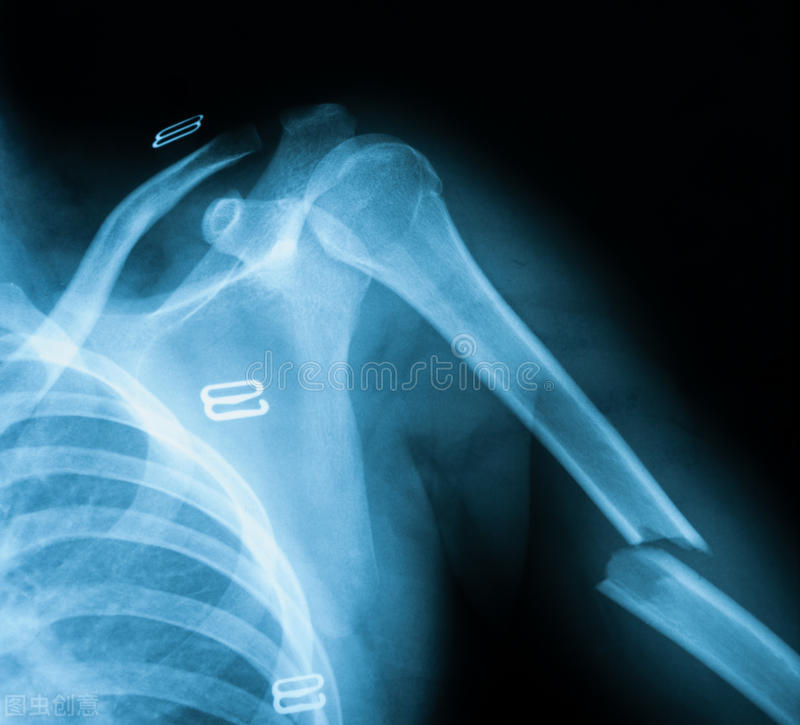

大学生都能骨质疏松,可能很多人觉得很不可思议,而实际上确实发生了这样的问题。前段时间的一个病例,大二男生和室友掰手腕,突然咔吧一声,剧痛无比,来我们医院一查,前臂骨折了,而X线片上发现骨皮质非常薄,再一查骨密度,还是明显的骨质疏松。这个小伙子,平时没有任何运动爱好,不打球也不游泳,最爱宅宿舍,熬夜打游戏,从不喜欢喝牛奶,也不喜欢豆制品。

首先要说的是,掰手腕会引起肱骨骨折,不只是因为骨质疏松。主要是因为肱骨不能承受太大的旋转剪切力,而同时伴有骨质疏松的话,骨折风险就更大了。

然后,掰手腕引起的骨折,篮球足球运动中小腿骨折,剧烈*力暴**引起,都不能称为脆性骨折。例如NBA球星保罗乔治比赛中,落地剪切力过大,小腿胫腓骨骨折,还有前段时间UFC综合格斗比赛中,一名选手惨遭断腿,他们作为顶级运动员,每天坚持锻炼,不可能有骨质疏松,所以这种情况下的突发意外骨折,哪怕是自己主动发力引起的,也不属于骨质疏松性骨折。脆性骨折发生在腕部、肩部、髋部和脊柱。例如桡骨远端骨折、肱骨近端骨折、股骨近端骨折、椎体压缩性骨折等。